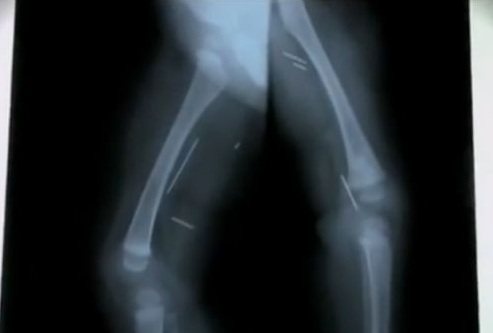

Лекарите в града Арекипа, в южната част на Перу, открили осем метални игли в тялото на седеммесечно момиче. Все още няма обяснение как иглите са достигнали до бебешкото тяло, а полицията разследва случая., предполага се, че детето е било обект на популярните в Перу вуду магии, съобщава Struma.com като се позовава на mk-news.Това е първият подобен случай в болницата Хонорио Делгад. Много е сложен и няма логично обяснение - каза директорът на болницата Цеуар Линарес. Той обяснил, че майката е завела бебето в болницата, защото много плачело

- След рентгенови изследвания открихме, че в тялото на бебето има игли за шиене и че, за щастие, не са навредили на нито един от органите - добавил той.

Предполага се, че иглите, които вече се намират в краката и в гръдния кош на момичето, са забодени от възрастен човек. За понеделник е планирана операция на детето, чието здравословно състояние, засега, е стабилно.